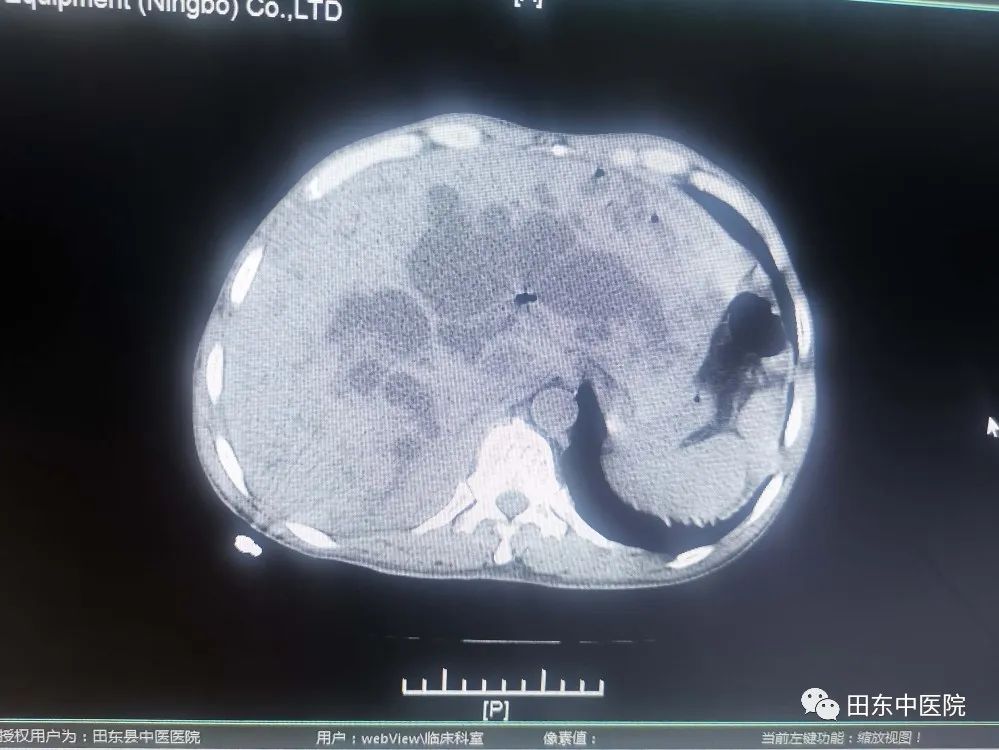

患者入院时有腹部剧痛、黄疸、寒战高热等症状,通过腹部CT增强、磁共振增强+胆道水成像等检查后,发现患者有:1、急性梗阻性化脓性胆管炎 2、脓毒血症 3、感染性休克 4、梗阻性黄疸 5、腹膜炎等多项急危重症,病情岌岌危重,急诊行PTCD引流术,经积极抗感染、扩容、抗休克、护肝退黄等措施把患者从死亡边缘抢救过来。